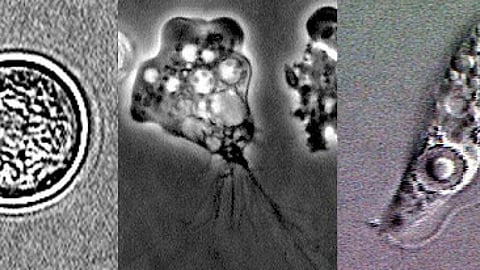

नेगलेरिया फाउलेरी एकल-कोशिका वाला जीव, जीवजगत का सबसे छोटा सदस्य है, इसको जलवायु परिवर्तन खासकर गर्मी बढ़ने से फैलने में मदद मिल रही है। बैज्ञानिक मानते है कि नेगलेरिया गर्म पानी में सबसे अच्छी तरह से बढ़ता है - 30 डिग्री सेल्सियस से ऊपर का तापमान, और 46 डिग्री सेल्सियस तक का तापमान सहन कर सकता है। यह इसे गर्म जलवायु में फैलने के लिए उपयुक्त बनाता है।

जब अमीबा युक्त पानी नाक के जरिए शरीर में प्रवेश करता है, तो यह लोगों को संक्रमित करता है। यह आमतौर पर तब होता है जब लोग झीलों और नदियों में तैरते हैं या गोता लगाते हैं। अमीबा नाक से घुसकर मस्तिष्क तक पहुंचता है, जहां यह मस्तिष्क के ऊतकों को नष्ट कर सकता है। इसे “प्राइमरी अमीबिक मेनिंगोएन्सेफलाइटिस” (Primary amebic meningoencephalitis) कहा जाता है, और यह जानलेवा हो सकता है।